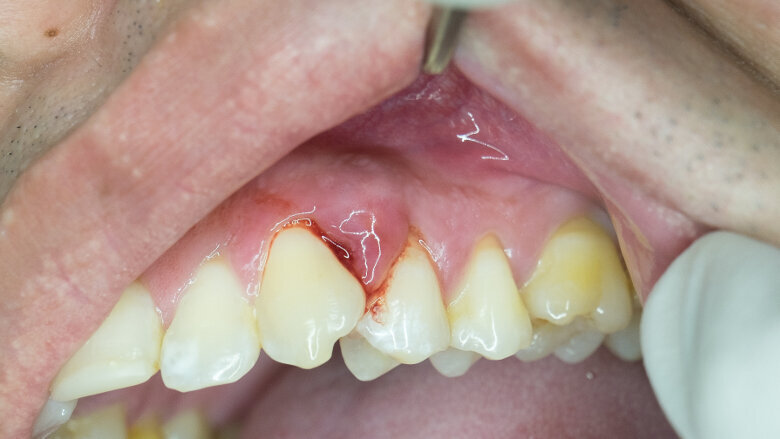

La présente étude s’est appuyé sur des échantillons provenant de l’étude ARIC (Atherosclerosis Risk in Communities) qui a suivi 8 275 sujets d'un âge moyen de 63 ans. Aucun des participants n'était atteint de démence au départ. Les chercheurs ont évalué les participants afin de déterminer s'ils souffraient de troubles cognitifs légers et de démence et ont effectué un examen parodontal complet qui comprenait la mesure de la profondeur de sondage parodontal, des saignements et de la récession. Ils ont ensuite établi des regroupements en fonction de la gravité et de l'étendue de leur maladie parodontale et du nombre de dents perdues (ou remplacées par des implants).

Au début de l'étude, 22 % des participants ne souffraient d’aucune maladie parodontale, 12 % avaient une maladie parodontale légère, 12 % une inflammation parodontale grave et 8 % avaient un faible degré de perte de dents. Certains des participants, 12 %, avaient une maladie parodontale au niveau des molaires, 11 % avaient une perte de dent sévère, 6 % avaient une maladie parodontale sévère et 20 % étaient complètement édentés. À la fin de l'étude, les chercheurs ont évalué 4 559 des 8 275 participants qui avaient été suivis pendant 18 ans en moyenne.

Les résultats ont montré que, dans l'ensemble, près d'un cinquième des participants, soit 1 569 personnes, ont développé des signes de démence au cours de l'étude. Parmi eux, 14 % des participants avaient des gencives saines et une dentition complète, 18 % avaient une maladie parodontale légère, 22 % avaient une maladie parodontale grave et 23 % étaient édentés.

Les participants édentés présentaient un risque environ deux fois plus élevé de troubles cognitifs légers et de démence que ceux ayant des gencives saines et une dentition complète, tandis que les participants atteints d'une maladie parodontale intermédiaire ou grave et n'ayant que quelques dents présentaient un risque 20 % plus élevé de déclin cognitif par rapport au groupe sain. Les risques ont été évalués après que les chercheurs aient pris en compte d'autres facteurs susceptibles d'influer sur le risque de développer une démence, notamment le diabète, un taux de cholestérol sanguin élevé et le tabagisme.